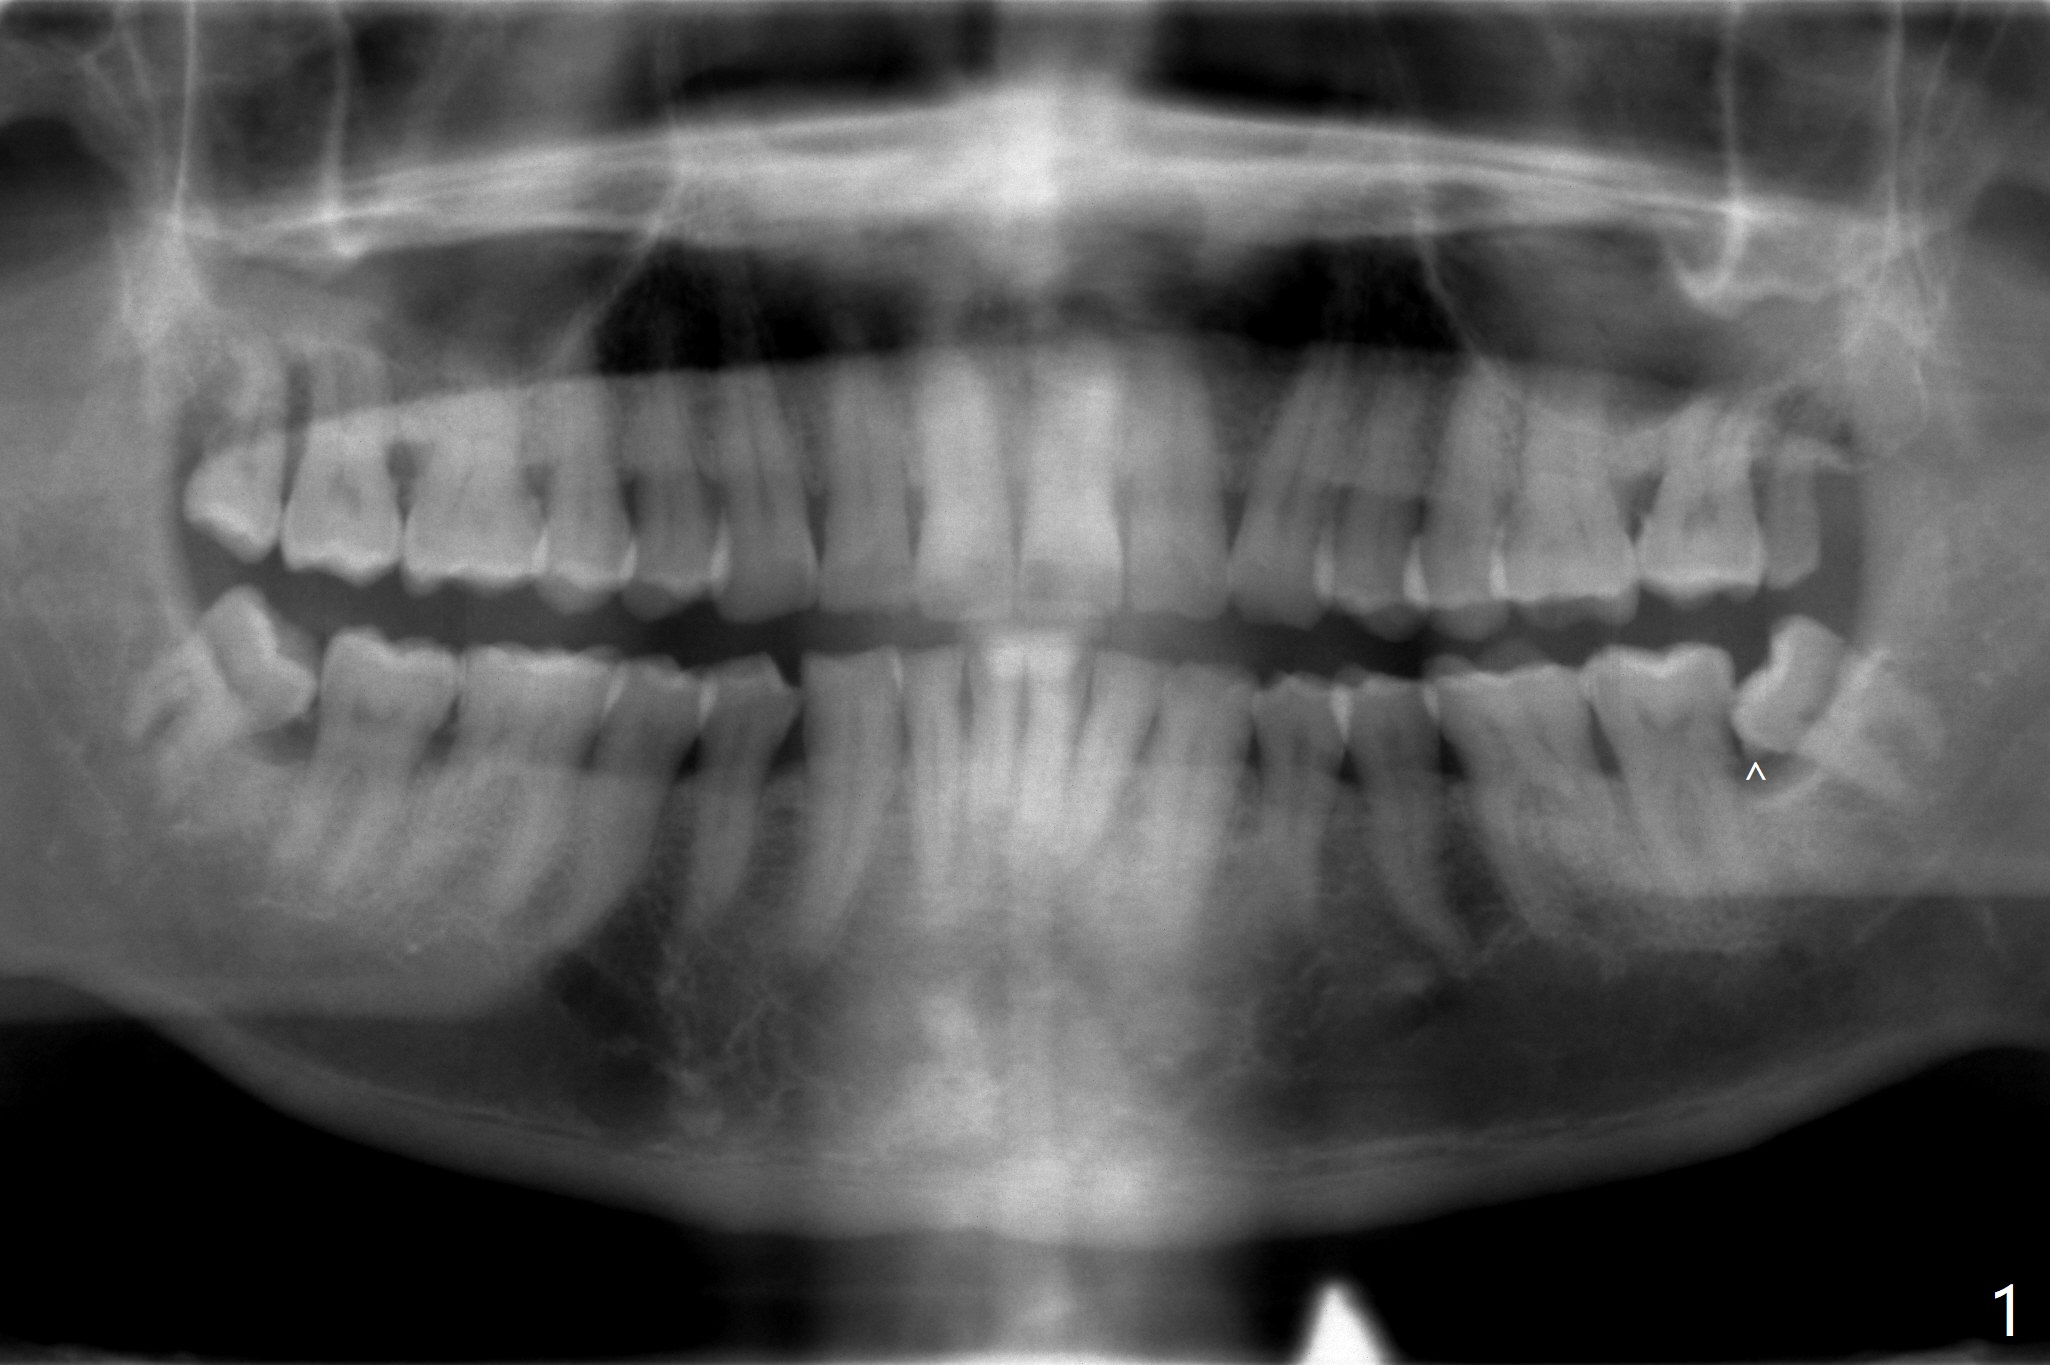

A 55-year-old man, smoker 1/2 ppd, has chronic periodontitis with heavy calculus between #17 and 18 (Fig.1). Six month post SRP, one piece of Osteogen plug is placed in each socket of #17 and 32 to promote bone growth and prevent dry socket (Fig.2). The bone is dense; the teeth needs sectioning several times before extraction.